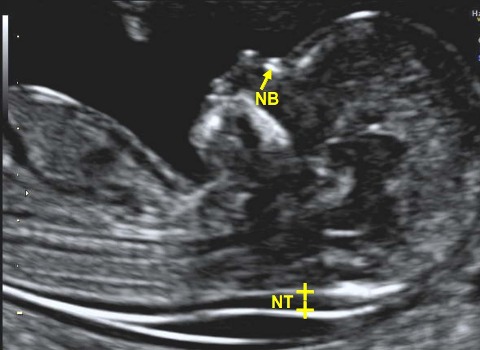

At Ultracare Diagnostic, we understand the importance of your health and the essentiality of accurate diagnosis. Therefore, we offer you comprehensive care and a non-invasive Ultrasound test that helps determine how well your body organs are functioning and if there are any abnormalities present. This helps the doctor to provide you with an accurate diagnosis and treatment for the same

We offers Best Services With Experienced hand on Sonology